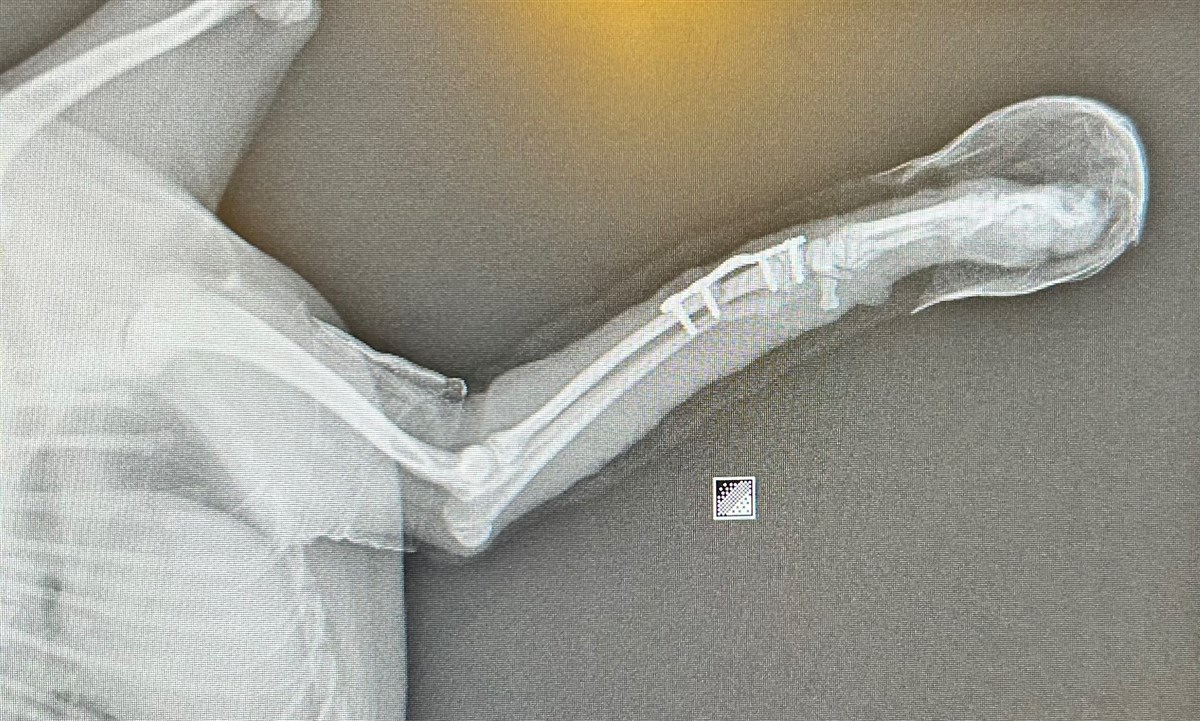

- Help Onze Puppy Haar Pootje Terug Te Krijgen 🐾💔Onze lieve puppy heeft dringend een operatie nodig. Ze is ongelukkig van de bank gesprongen en heeft haar pootje zo ernstig gebroken dat er een metalen plaat geplaatst moet worden. De ingreep moet uitgevoerd worden door een orthopedisch chirurg en is helaas onvermijdelijk.

Omdat ze nog volop in de groei is, zal er na de eerste operatie ook een tweede operatie nodig zijn om de plaat weer te verwijderen. Daarna volgt nog een revalidatieproces om haar helemaal te laten herstellen.